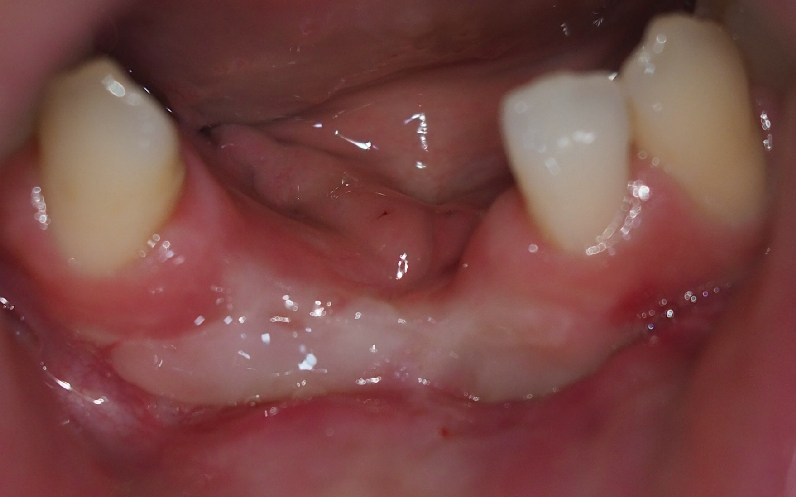

▲ FGG 완료 후 구강 사진

위의 사진은 잇몸 이식이 완료된 후 회복된 상태입니다

색상의 차이는 다른 부분의 조직이기 때문입니다!